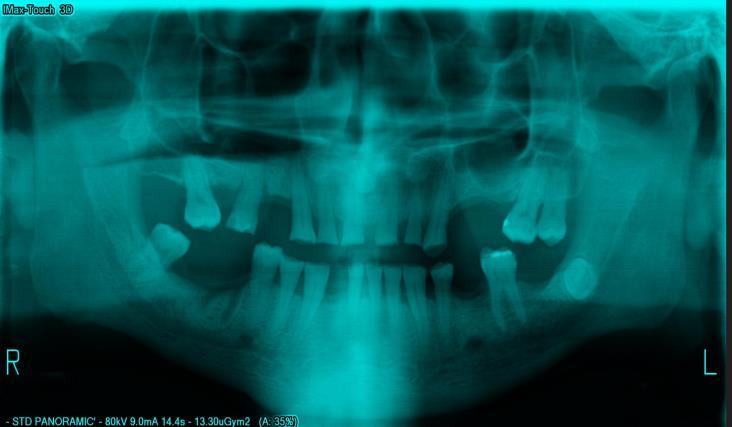

2.1. DATA COLLECTION

TheinputdatasetcomprisespanoramicX-ray(OPG)imagescollectedfromanopen-sourceKaggledataset.Additionally,raw imageswerecapturedusingaXiaomiRedmiNote9Pro64MPcameratoexpandthedataset.Theimagesrepresentpatients of various age groups and genders, with a focus on middle-aged individuals. Some images exhibit blue and grey tints, highlighting variations in imaging conditions. The dataset ensures diversity by including images of children, men and women,capturingarangeofdentalstructures.Thecollectedimagesserveasinputforthesegmentationmodels,providing real-worldvariabilityessentialforrobustmodelperformance.